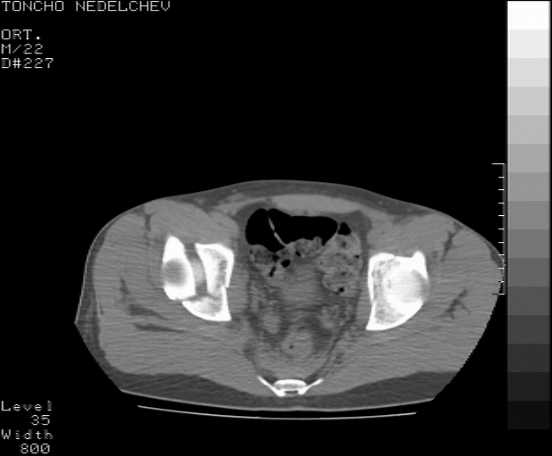

Here are some more axial images. What is your opinion as for the timing of the operative treatment?

The details of the fracture are not so clear from the images sent...would you be able to send along an AP and Judet images as well as some additional axial images above and below the joint?

Without complete CT images and/or oblique radiographs, it's difficult to answer your question definitively, but it appears that there may not be a posterior wall fracture that requires a posterior approach. A successful reduction through an ilio-inguinal approach will have a faster recovery, and not risk SGN injury or heterotopic ossification.

Yordan! In this case position of bone fragments is quite good. We

prefer to use miniinvasive technique. We fix posterior column by can. screw and put 3mm pin with distal thread to the anterior column. Next day after the surgery he may start walking with crutches. 3 month after the surgery we remove the pin. In cases of maleolar fractures we use

angle stable plates to lat. mal. and pins or screws and if syndesmosis is intact - full loading is not forbidden.